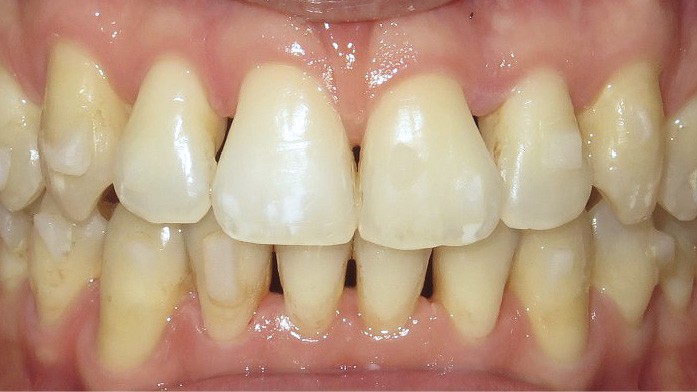

Après avoir traité les troubles transversaux et antéro-postérieurs, l’action orthodontique s’est concentrée sur les défauts d’alignement, grâce à des gouttières orthodontiques (fig. 4). L’avantage des gouttières par rapport aux dispositifs multi-attaches vestibulaires, c’est que l’alignement se fait avec une avancée moindre des bords libres des incisives et qu’elles permettent de définir plus précisément où l’on peut stripper pour gagner de la place et réduire les triangles noirs. En outre, le nettoyage des dents est facilité, ce qui est intéressant chez les patients ayant des atteintes parodontales.

Discussion (fig. 5a- i)

La difficulté a été de garder le patient motivé, car les trois temps du traitement se sont ajoutés (2,5 ans) et le traitement reposait beaucoup sur sa coopération (dispositifs amovibles à savoir les élastiques et les gouttières).

Cependant, le patient est récompensé des choix qui ont été faits, car désormais son sourire est harmonieux avec une occlusion équilibrée. L’augmentation des triangles noirs a été limitée grâce aux soustractions amélaires au niveau des faces proximales des dents antérieures. En revanche, pour parfaire le résultat au niveau esthétique, des apports de composites ont été réalisés, car les dents de devant étaient très pincées au niveau cervical.

Le traitement est stable dans le temps, car les contacts occlusaux sont harmonieux ainsi que les fonctions et les déplacements ont été surtout coronaires.